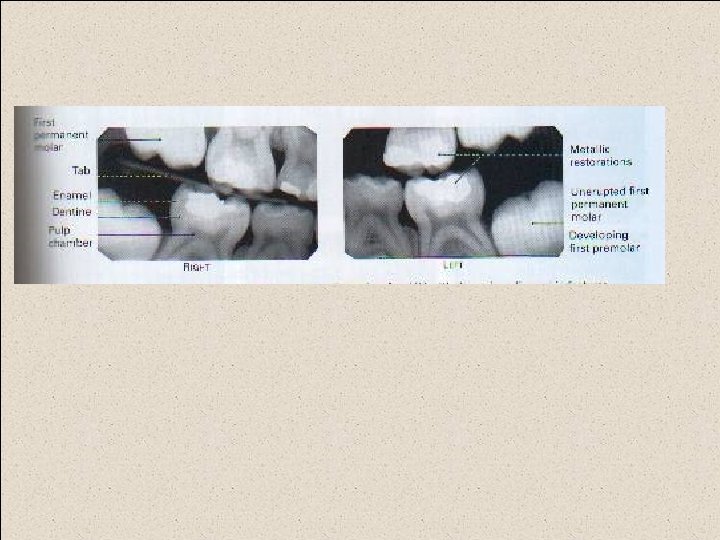

Technique requirements when using a tab attached to the image receptor The appropriate sizes film packet or phosphor plate is selected and the tab attached, orientated appropriately for horizontal or vertical projections: Large film (31*41) or long film (53*26) is used for adult, and small film (22*35) for children under 12 years.

The patient is positioned with the head supported and with the occlusal plane horizontal. The shape of the dental arch and the number of film required are assessed. The operator holds the tab between thumb and forefinger and insets the image receptor into the lingual sulcus opposite the posterior teeth.

The anterior edge of the image receptor should be positioned opposite the distal aspect of the lower canine

The tab is placed on to close the teeth firmly together on the tab. The patient closed the teeth firmly together on the tab. The operator assesses the horizontal and vertical angulations and positions the X-ray tubehead so that the X-ray beam is directly through the contact areas, at rught angles to the teeth and image receptor, with an approximately 5 o-8 o downward vertical angulation